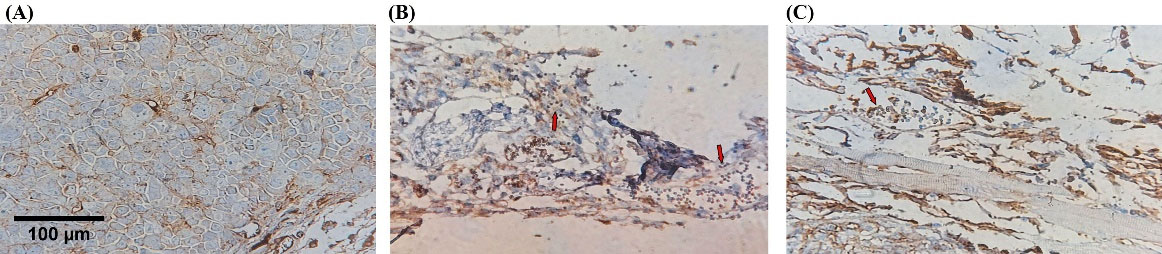

While the NK cells were injected intratumorally, the surface marker of NK cells, hCD56, was evaluated by IHC to verify NK cell permeation to the tumor microenvironment. The control and MC group did not receive human NK cells, so expressing the hCD56 was definitely negative. Cytotherapy and combination groups demonstrated a different pattern of hCD56 expression due to the Allred score. The proportion score in the cytotherapy group indicated more than 30% immunoreactivity, and the intensity was intermediate positive (3 of 4 tumor samples). Still, the combination group demonstrated lower immunoreactivity, almost 10%, and the intensity was weakly positive (3 of 4 tumor samples). Evaluation of IHC slides demonstrated the aggregation of adoptive NK cells in the tumor margin. The cells could not properly infiltrate to tumor center in both experimental groups (Table 2, Fig. 6).

Fig. 6.

Adoptive NK cells infiltration injected intratumorally. IHC evaluated Tumor-infiltrating NK cells with anti-CD56 antibody in tumor microenvironment. Cytotherapy and combination groups demonstrated a different pattern of hCD56 expression (Red arrow showed immunoreactive cells). (A) Negative control, (B) Combination, (C) NK cell therapy. Scale bar: 100 μm, 400X magnification.